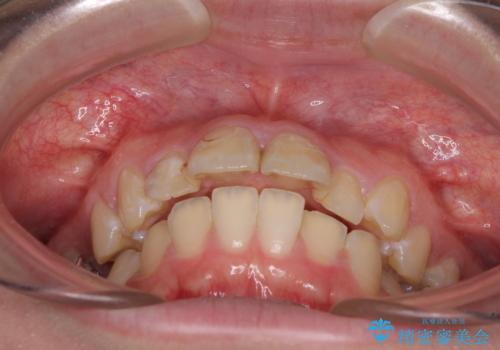

- 上の前歯の出っ歯とでこぼこの歯並びを気にして来院された患者様です。

上下顎歯列ともに前方に突出していましたが、上顎歯列がより前方位にあったため、上顎左右は第1小臼歯を、下顎左右は第二小臼歯を抜歯することとしました。

下顎は過剰歯が埋伏しており、それが原因となってスペースが閉じなかったため、途中で抜歯して速やかに仕上げました。